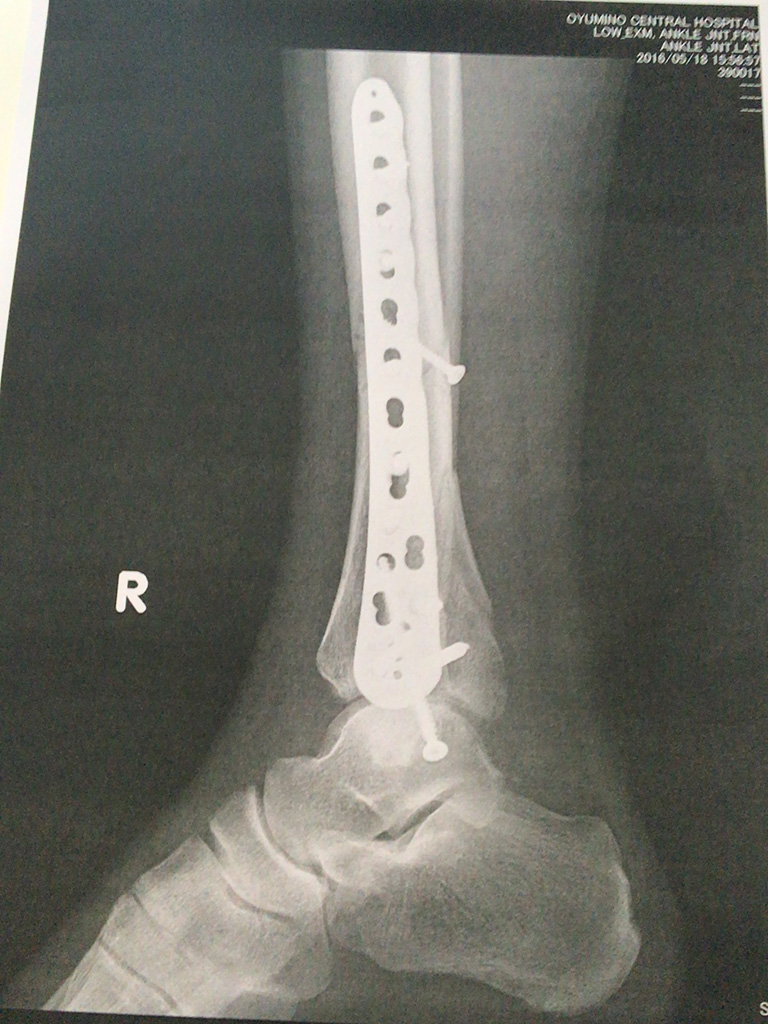

退院するに当たって昨日最後に撮ったレントゲンのコピーをもらったけど、相変わらず見ても治っているのかいないのか…(笑)

昨日から右足は10kgまで荷重を掛けても良いということになっていて、骨に直接力が加わると治りっぷりも加速するらしく、一昨日よりも明らかに痛みが減っているし、膝から下のいろんなところの動きがスムーズになってきている。